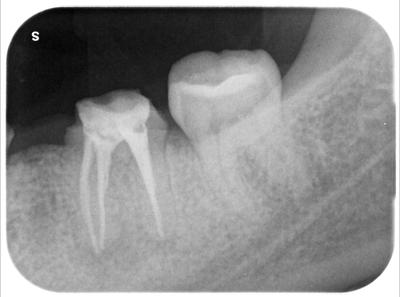

処置後数日で症状は消失。

処置開始2週目で問題消失のため根管充填。

根尖部の陰影も消失傾向に見える。

前医が必要以上に根管拡大していたと思われるため、一部MTAで充填している。

ここまでの治療時間トータル2時間。